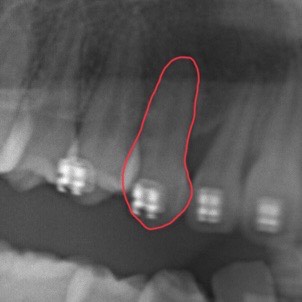

矯正治療が進んだ後のレントゲンがこちらです。

埋伏した歯は根の形成が終了するとその位置から動かすことがより困難になる可能性があるため、子どもの矯正治療でアプローチすることがお勧めです。